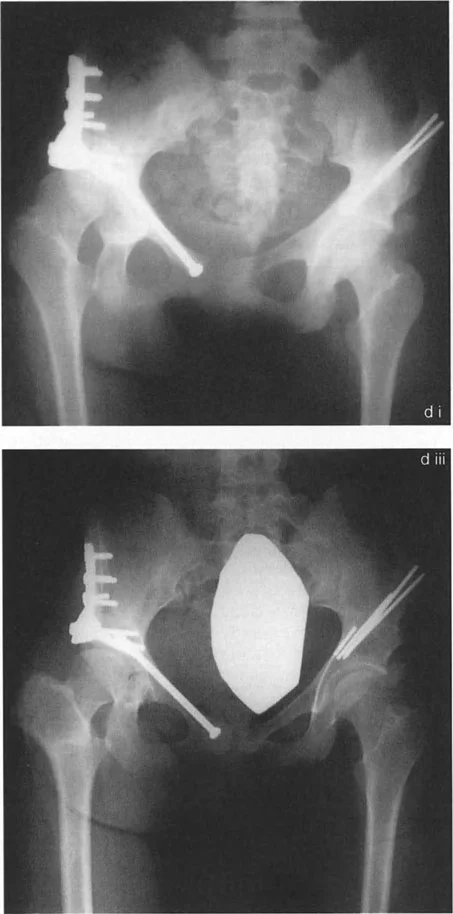

صور توضح حالة كسع الورك مع تضخم المدور الكبير قبل وبعد إجراء قطع عظم واغنر، حيث يتم تصحيح المحاذاة ونقل المدور الكبير.

صور توضح حالة كسع الورك مع تضخم المدور الكبير بسبب مرض بيرثيز، وعلاجها باستخدام قطع عظم مورشر مع التثبيت الداخلي.

صور بالأشعة السينية لحالة فتاة تعاني من تشوه فحجي مع دوران داخلي وخلع جزئي، توضح التدخل الجراحي بقطع عظم فاروسي مع نقل المدور الكبير والتثبيت بمثبت خارجي، ثم النتيجة النهائية بعد التعافي.

صور بالأشعة السينية لحالة كسع الورك مع رأس فخذ بيضاوي، توضح كيفية تصحيح اتجاه المحور البيضاوي بقطع عظم فحجي لتحسين توزيع الحمل.